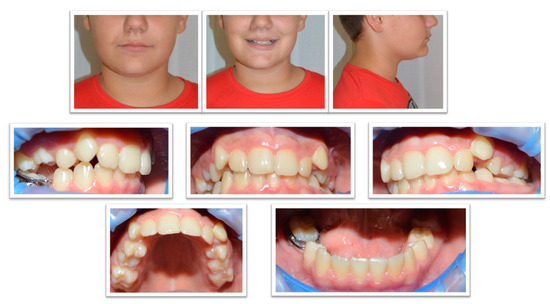

2. Case Report

2.1. Examination, Diagnostics, and Initial Therapeutic Management